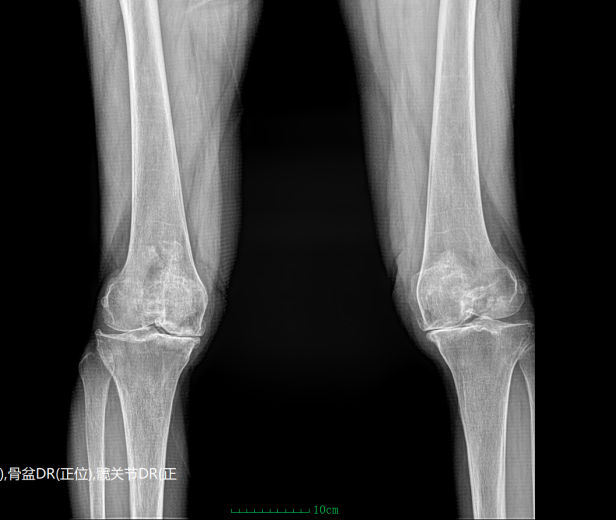

(术前)(术后)

程奶奶的膝关节问题已困扰她十多年。起初只是偶尔酸痛,家人以为是年龄增长带来的自然退变,并未在意。但半个多月前,病情明显加重——走几步路就疼痛难忍,上下楼困难,甚至夜间翻身都成了负担。在多家医院反复就诊却效果不佳后,家属焦急万分,最终慕名来到青田康馨医院。吴院长接诊后迅速完成系统查体,并结合影像学检查明确诊断为膝关节骨关节炎(内侧间室严重病变)。“软骨几乎磨没了,骨头直接摩擦,就像没有润滑的齿轮。”通俗而精准的解释,让家属一下明白了问题的根源。

面对手术,家属既期待又担忧。吴院长团队进行了多轮术前评估与讨论,量身制定了单髁置换方案,并耐心解释:“这就像补牙,哪里坏了补哪里,不需要全部更换。”该术式仅置换病变间室,最大程度保留正常结构,具有创伤小、出血少、恢复快的显著优势,尤其适合高龄患者。这一番细致讲解,逐步打消了家属的顾虑,也让他们重新燃起了信心。手术当天,吴院长主刀,通过约6–8厘米微创切口精准完成置换,手术过程顺利、出血极少,展现出高超的技术水平。